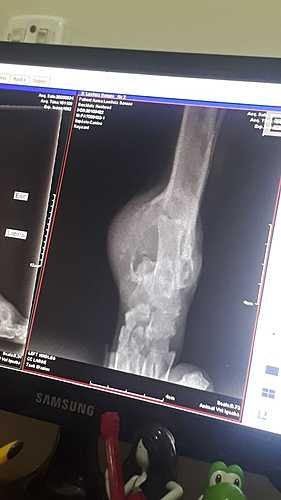

Olá pessoal, meu irmãozinho, Sansão, foi diagnosticado com osteossarcoma e precisará realizar uma cirurgia de amputação da patinha onde está localizado o tumor.No momento estamos sem condições de arcar com os custos da cirurgia. Já realizamos os exames de raio x da área afetada e do pulmão e coração para saber se há metástase ou não, e graças a Deus, não há metástase. Estamos tratando da dor que essa doença causa com medicamentos prescritos pelo veterinario. Ele tambem esta tomando um suplemento vitamínico para impedir a evolução da doença.

Sobre o Sansão: Sansão tem 10 aninhos e sempre foi um cachorrinho muito alegre, ativo, carinhoso, que ama correr e andar de carro pegando um ventinho na janela. Porém, de uns tempos pra cá ele começou a mancar muito. Levamos ele ao veterinário, que pediu pra fazer o exame de Radiografia, onde ele foi diagnosticado com essa doença, o osteossarcoma. Ele está sendo medicado para dor, mas não é mais o mesmo, ele ama passear, mas até em nossos passeio ele fica aparentemente triste, tudo por conta da dor. Ele é o MELHOR cachorro que eu conheci e tenho o prazer de conviver e não suporto vê-lo sofrer tanto assim. Sobre o tumor ósseo (osteossarcoma): O osteossarcoma é um tumor maligno ósseo que é mais notado em cães. Esse tipo de anomalia é caracterizado por acometer diferentes órgãos e regiões do corpo do animal, sendo bem agressivo e doloroso. A terapia que é mais usada nesse tipo de tratamento é na amputação seguida de quimioterapia uma vez que melhora bastante os resultados.Podem me solicitar os comprovantes de gastos, envio de fotos, vídeos e qualquer outro tipo de confirmação ou informação, deixo meu número de WhatsApp: (21) 971928043 pra contato.Toda ajuda é SUPER bem vinda, serei eternamente grata.